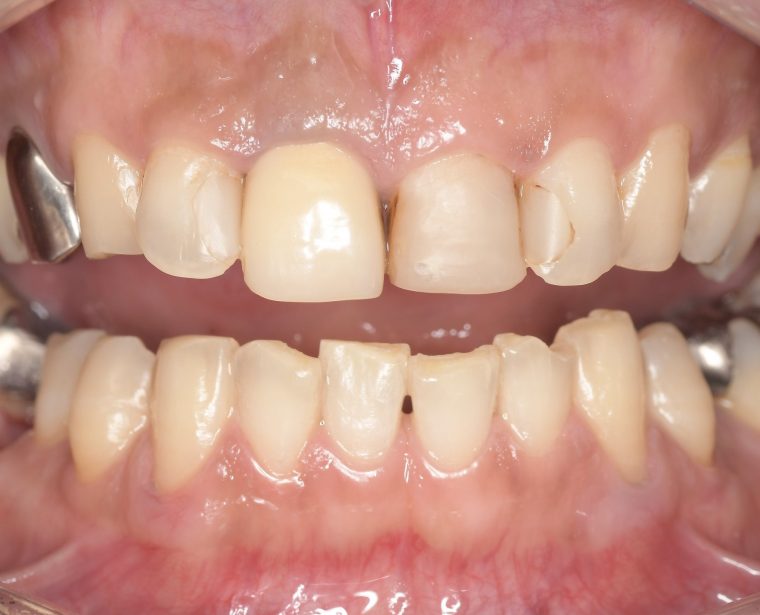

CASE 2

Before

After

基本情報

| 年齢・性別 | 30代・男性 |

| 主訴 | 歯石を取りたい |

| 治療内容 | 超音波スケーラーでの歯石除去 |

| 治療期間 | 60分 |

| 治療費 | 初診料を含め約4,500円 |

| リスク・副作用 | 歯ぐきに違和感や痛みを覚える場合がある。 1週間程度、歯を磨くといつもより出血することがある。 腫れていた歯ぐきが引き締まることで歯ぐきが下がった様に見える。 歯ぐきが下がることで歯がみしやすくなることがある。 一時的に歯の動揺(ゆれ)が増す場合がある。 |